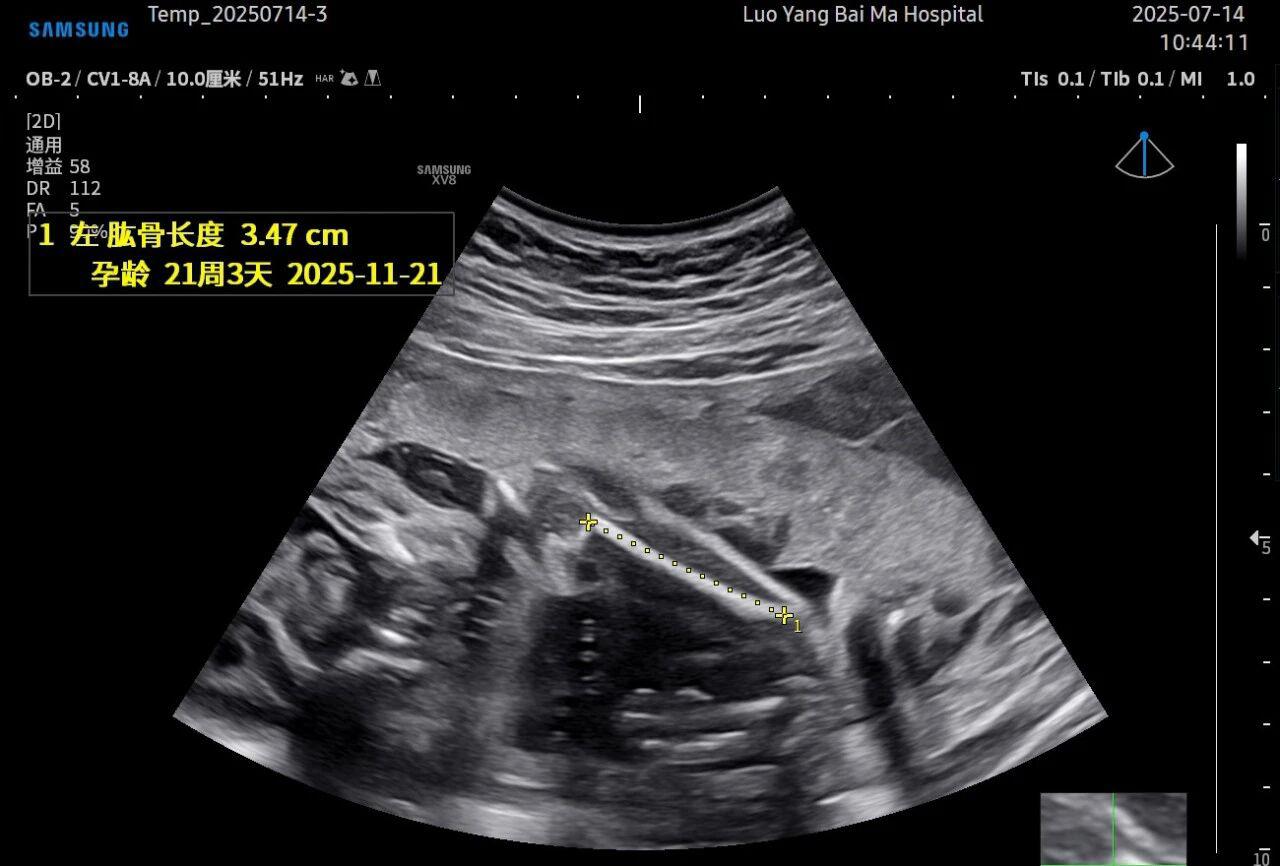

3. AI智能辅助,提升诊断效率与客观性

这是5D技术的核心优势之一。系统内置了强大的智能化大数据分析功能和AI辅助诊断工具。例如,在进行胎儿颈项透明层(NT)测量、胎儿长骨(LB)测量等关键生物学指标评估时,5D智能系统可以自动识别解剖层面、智能勾勒测量范围并进行计算。这不仅大大缩短了检查时间,更重要的是,它通过标准化的智能算法减少了因人为操作可能产生的误差,使诊断结果更加客观、可靠。